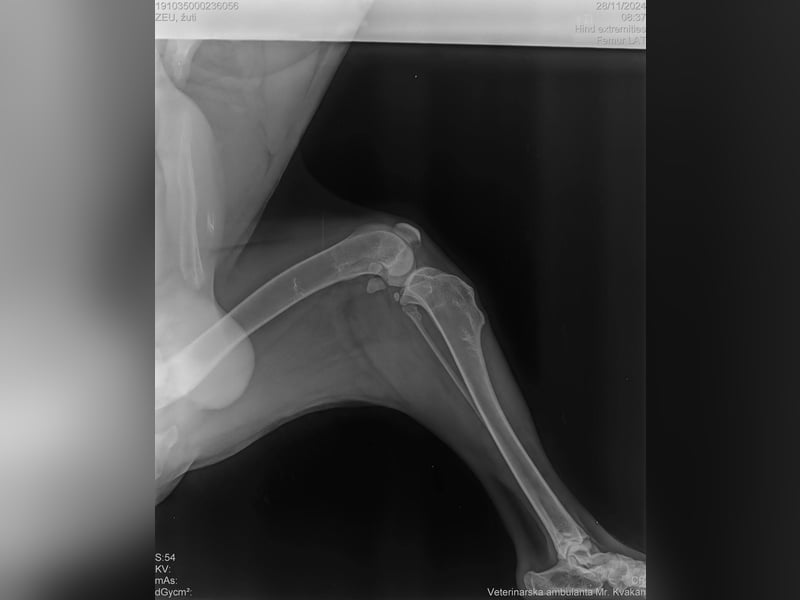

Eines seiner Hinterbeine war gebrochen, es wuchs wieder zusammen, aber es ist nun schwächer als die anderen und es fällt ihm nicht ganz leicht auf dem Bein aufzutreten. Doch Elijah hält sich wacker und sucht nun dich: einen Freund, der ihm Sicherheit und Geborgenheit bietet und ihm zeigt, wie schön das Leben ist.